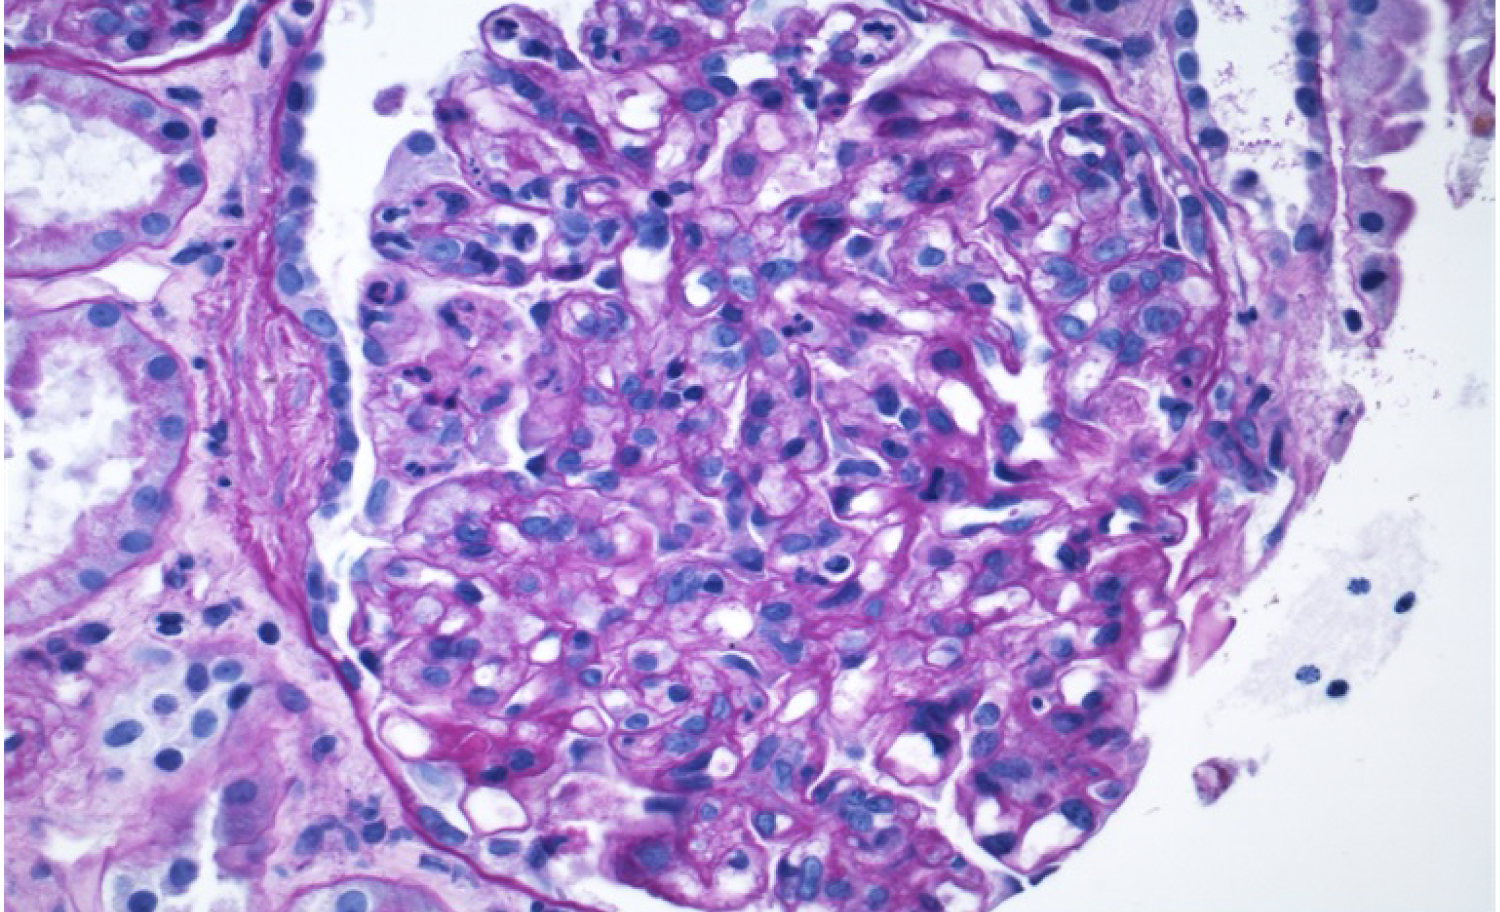

A 60-year-old man with a history of remote deep vein thromboses and HCV infection presented with dyspnea and myalgia that he had been experiencing for one week. His HCV infection nine years prior was treated with ledipasvir/sofosbuvir, resulting in sustained virologic response (SVR). At the time of admission, his vital signs were unremarkable except for a blood pressure of 162/76 mmHg. Physical examination demonstrated expiratory wheezing bilaterally, 1+ pitting edema, and bilateral petechial rash of the lower extremities (Figure 1). Urinalysis revealed proteinuria (100 mg/dL) and hematuria (more than 100 RBC/hpf on microscopy with dysmorphic appearance). The patient’s serum creatinine level (2.41 mg/dL; baseline 1.1 mg/dL) and rheumatoid factor level (207 IU/ml) were elevated, while the complement component 3 (C3) and component 4(C4) levels were decreased (71 mg/dL and < 5 mg/dL, respectively). Antineutrophil cytoplasmic antibody was negative, and HCV viral load was undetectable. Anti-glomerular basement membrane and antiphospholipid antibodies were also negative. Chest X-ray revealed appreciable bilateral pulmonary congestion, and transthoracic echocardiogram showed an ejection fraction of 54%. The patient developed hemoptysis for which a subsequent bronchoscopy confirmed diffuse alveolar hemorrhage. Serum cryoglobulins were detected, and he was treated with plasmapheresis for five days and a short course of pulse dose methylprednisolone (1 g/day) for three days. Renal biopsy confirmed cryoglobulinemic glomerulonephritis with a membranoproliferative pattern of injury (Figure 2 and Figure 3). The patient was subsequently managed with rituximab infusions at a dose of 375 mg/m2 per week over four weeks and a prolonged prednisone taper, which resulted in improved renal function and clinical status. Renal function normalized after a few months. Rheumatoid factor became undetectable two weeks after the first four-doses of rituximab. Both C3 and C4 returned to normal range 12 weeks after rituximab.

Figure 2: Kidney biopsy sections demonstrated cryoglobulinemic glomerulonephritis with hyaline pseudothrombi, and membranoproliferative glomerulonephritis injury pattern (x400, H&E stain). View Figure 2